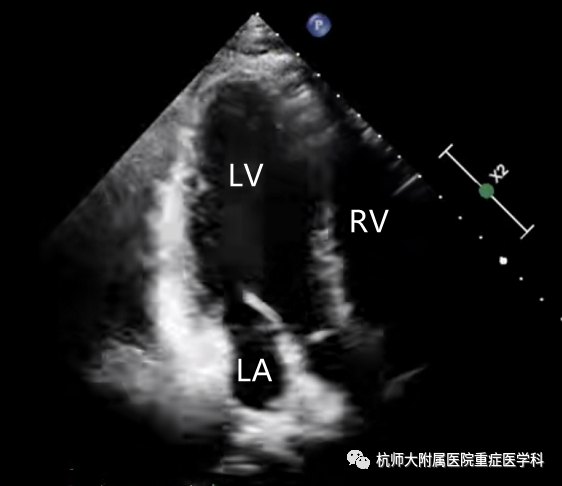

c.心尖四腔心切面:位置选择:心尖处,超声探头声束朝向患者右肩方向指向心底;操作过程中在胸骨旁长轴切面沿左心室向心尖滑动;当室间隔刚刚消失时,将超声探头旋转90°~120°;将超声探头向前倾斜,声束指向右肩,找到标准平面。

主要评估内容:(1)各腔室大小、比例;(2)室壁的运动;(3)测量射血分数;(4)二尖瓣和三尖瓣瓣膜的形态结构及瓣口血流情况。